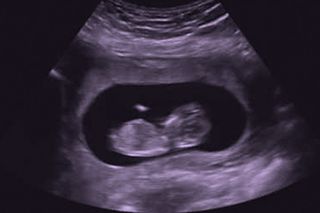

So your friend decides to forget the “12 week rule” and tells her family and social networks she is pregnant. She knows the stats – one in four pregnancies ends in miscarriage – but she wants to have the support of family and friends around her in case she needs it.

Then the worst happens: she miscarries. And she discovers many people around her, including health professionals, lack sensitivity when talking about the miscarriage. Some don’t even acknowledge her loss.

Miscarriage in Australia is defined as the loss of a foetus before 20 weeks. From a medical perspective, miscarriage is easily managed as a “routine pregnancy complication.” Emotionally, however, it can take a massive toll. As one interviewee in our yet-to-be-published research explained: